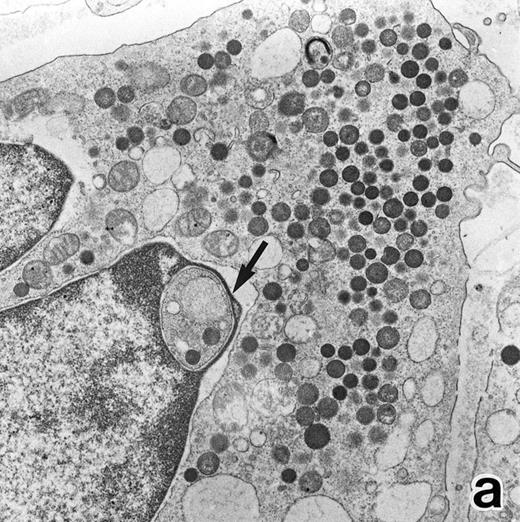

(a) A PMN in patient no. 2 after 10 days of ATRA treatment. The nuclei are irregularly lobulated, with some of them being connected by nuclear filamentous structures, and heterochromatin is condensed along the nuclear membrane. (Original magnification × 13,100.) (b) Higher magnification of a portion of the cell in (a). The cytoplasmic granules are large and spherical, and some of them contain flocculent material and central cores with higher electron density. (Original magnification × 20,200.)

Common morphological changes of bone marrow leukemia cells were observed during ATRA treatment. After 1 week of ATRA treatment, leukemic cells showed heterochromatin condensation and nuclear lobulation (Figs 3 and 4). Although the lobulated nuclei of some cells resembled those of PMNs, these nuclei were irregular in shape and nucleoli were occasionally present. The lobulated nuclei often had nuclear blebs (Fig 3a) or were connected by thin nuclear material (Fig 4a), called filamentous connections,13 that consisted of heterochromatin delimited by the nuclear membrane. In addition to these changes, the irregularly shaped primary granules became morphologically normal. This was most evident in patient no. 1, in whom the majority of both Auer rods and irregularly shaped inclusions, as shown in Fig 2, dramatically vanished and the remaining primary granules appeared normal, being spherical in shape and relatively homogeneous in size (Fig 3a), although abnormal primary granules and/or Auer rods were infrequently observed in some cells. Rarely, a structure composed of an Auer rod coupled with a primary granule was found, appearing as though the seemingly normal primary granule had emerged from the Auer rod (Fig 3b). Type I primary granules still predominated in all patients, but type II primary granules with a nucleoid structure were rarely observed in patients no. 1 and 2. Some maturing neutrophils with abnormally shaped lobulated nuclei in patient no. 2 possessed unusual, possibly immature, primary granules containing central electron-dense material (Fig 4a and b), indicating asynchronous maturation of nuclei and cytoplasmic granules.